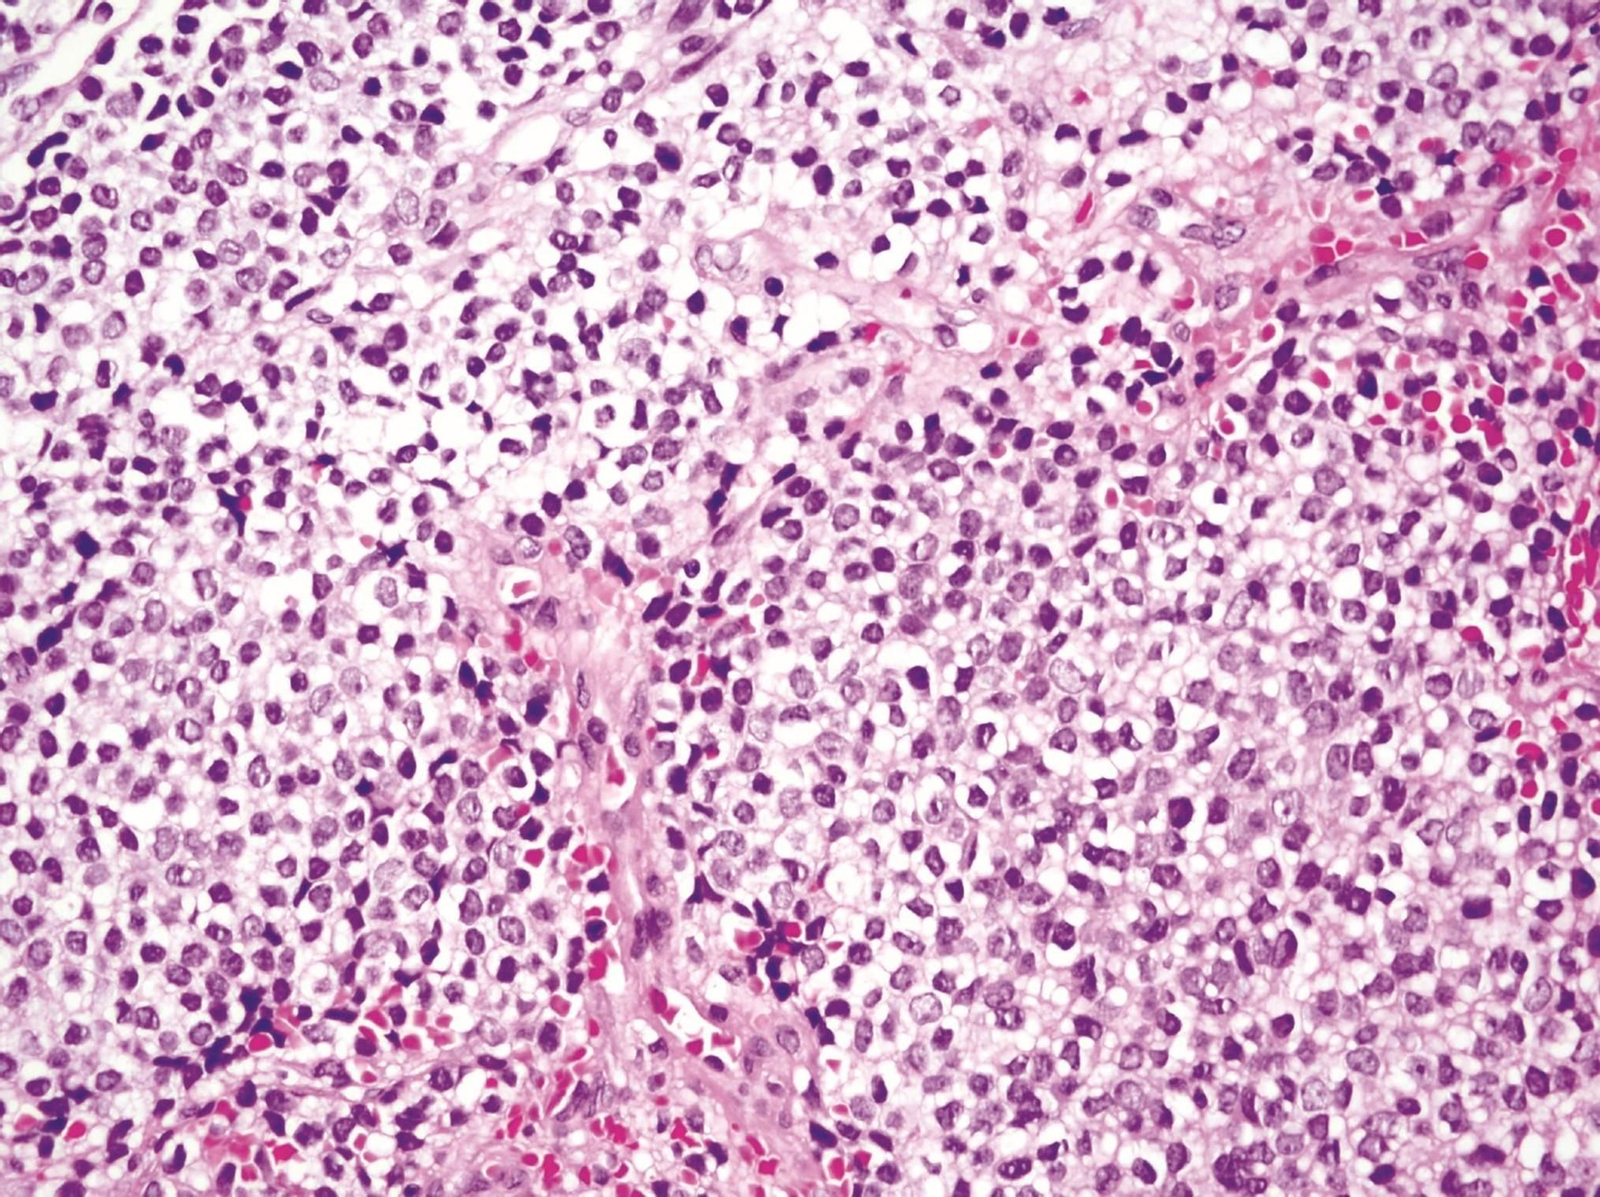

Un equipo del Instituto de Biomedicina de Sevilla (IBiS) ha identificado un nuevo mecanismo molecular que explica la elevada sensibilidad del sarcoma de Ewing —un tumor óseo agresivo que afecta principalmente a niños y adolescentes— a determinados fármacos quimioterápicos, como el irinotecán. Los resultados, publicados en la revista Oncogene, abren la puerta a estrategias más personalizadas y eficaces para el tratamiento de este tipo de cáncer.

El sarcoma de Ewing está caracterizado por una alteración genética muy específica: la fusión de los genes EWSR1 y FLI1, que da lugar a una proteína quimérica oncogénica denominada EWS::FLI1. Esta fusión, además de iniciar y sostener el crecimiento tumoral, altera procesos celulares esenciales. En este estudio, los investigadores han descubierto que EWS::FLI1 secuestra a una proteína clave, DHX9, impidiendo su función natural en la resolución de algunas estructuras de ADN/ARN llamadas R-loops. Como consecuencia, las células tumorales acumulan estas estructuras, lo que conduce a inestabilidad genómica, estrés replicativo y muerte celular, especialmente tras el tratamiento con irinotecán, un inhibidor de la topoisomerasa I, que induce altos niveles de R-loops en la célula.

"Este trabajo nos ayuda a entender por qué algunos pacientes con sarcoma de Ewing responden especialmente bien a fármacos como el irinotecán. Pero, sobre todo, nos da pistas para estratificar mejor a los pacientes y diseñar ensayos clínicos con terapias combinadas más racionales y dirigidas", afirmó Enrique de Álava, jefe del Servicio de Anatomía Patológica del Hospital Universitario Virgen del Rocío e investigador responsable del grupo Patología molecular de los sarcomas y otros tumores del IBiS. "En un tumor tan complejo y agresivo como este, ganar precisión en el tratamiento puede marcar una diferencia real en la supervivencia".